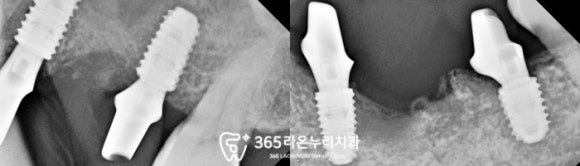

■ 4. 진행 과정

우선 식사가 어려우신

오른쪽 아래부터 진행을 시작했습니다.

이후에는 왼쪽 위 약해진 이를 뽑고

발치 즉시 식립을 진행하기로 했는데요,

생각보다 치근 끝에 염증이 크고

치조골 소실도 존재하여

뼈이식도 함께 동반했습니다.

상악동이라 불리는 해부학 구조를

조심스럽게 다루면서 식립을 마쳤으며

제일 뼈가 많이 녹고

흔들리는 어금니도 발치 후

픽스처를 심었는데요,

이때 골질이 약한 부위는 피하면서

단 3개의 픽스처만으로

4개의 저작기능을 할 수 있도록

힘을 분배하는 위치에 식립을 마쳤습니다.